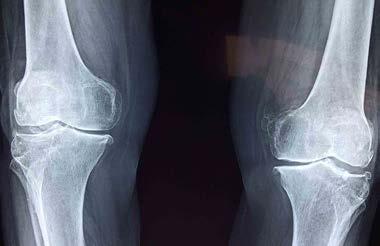

GENU RECURVATUM HIPEREXTENSIÓN DE LA RODILLA Dr. Abraham Machuca - P. 50 “EL COMERCIO DEL DOLOR” Libro de la Periodista Altagracia Ortiz P. 66 COSMESURGERY Publirreportaje P. 62 “SABES QUE ES SER PACIENTE MONORRENO” Dr. Wilton Cabrera - P. 64 ADICCIÓN A LOS VIDEOJUEGOS EN NIÑOS Lic. Consuelo García - P. 60 RADIOCIRUGÍA CON GAMMA KNIFE EN EL TRATAMIENTO DE LAS METÁSTASIS CEREBRALES P. 68 MAMOPLASTIA CON USO DE IMPLANTES DE POLIURETANO - P. 30 DONAR SANGRE UN ACTO ADMIRABLE P. 32 EFECTIVIDAD DEL TRATAMIENTO QUIRÚRGICO DE PIE PLANO VALGO FLEXIBLE - P. 34 CALLOS O VERRUGA PLANTAR - P. 38 ¿ES LA CIRUGÍA BARIÁTRICA, UNA CIRUGÍA ESTÉTICA? - P. 44 HALLUX VALGUS (JUANETES) - P. 46 LA EXPECTATIVA DE VIDA DEL HOMBRE PROMEDIO EN REPÚBLICA DOMINICANA - P. 48 PARÁLISIS DE BELL: PARÁLISIS FACIAL IDIOPÁTICA - P. 40